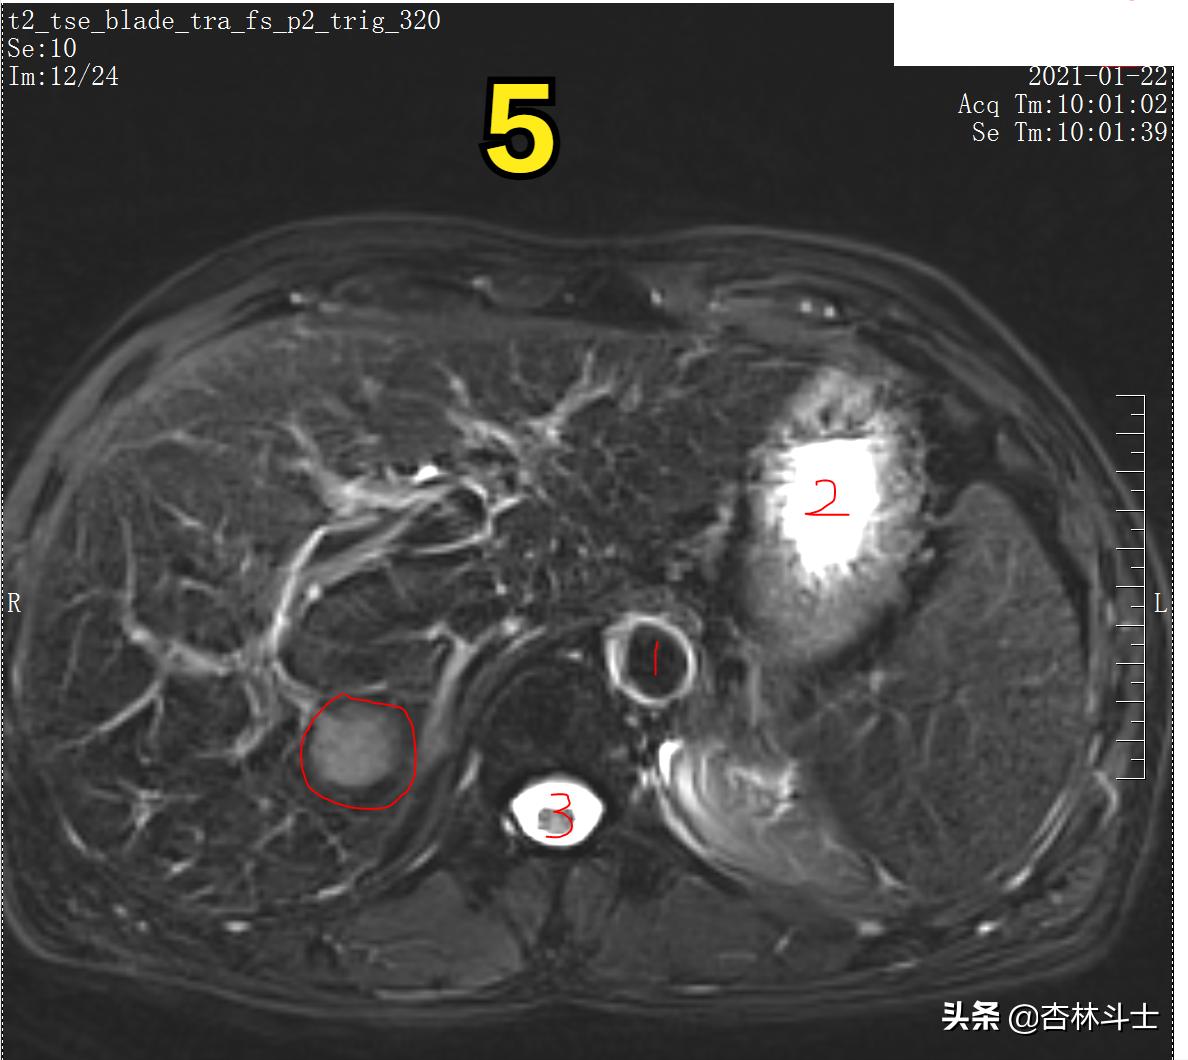

图5 T2加权压脂像

图5 T2加权压脂像,病灶呈稍高信号影,压脂像目的是调整成像参数,将脂肪的高信号压下去,呈低信号,突出显示炎症、水肿、积液等高信号影。图中1、为腹主动脉,其内血液呈极低信号原因为磁共振“流空效应” 2、胃腔,高信号为胃腔内的水 3、椎管 高信号为脑脊液,中等信号的为脊髓。